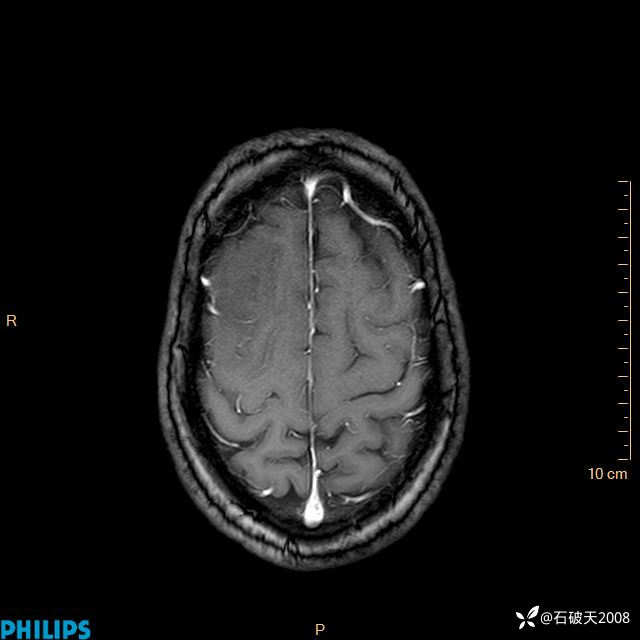

2024.2.21MR

增强轴位

增强冠状位

增强矢状位